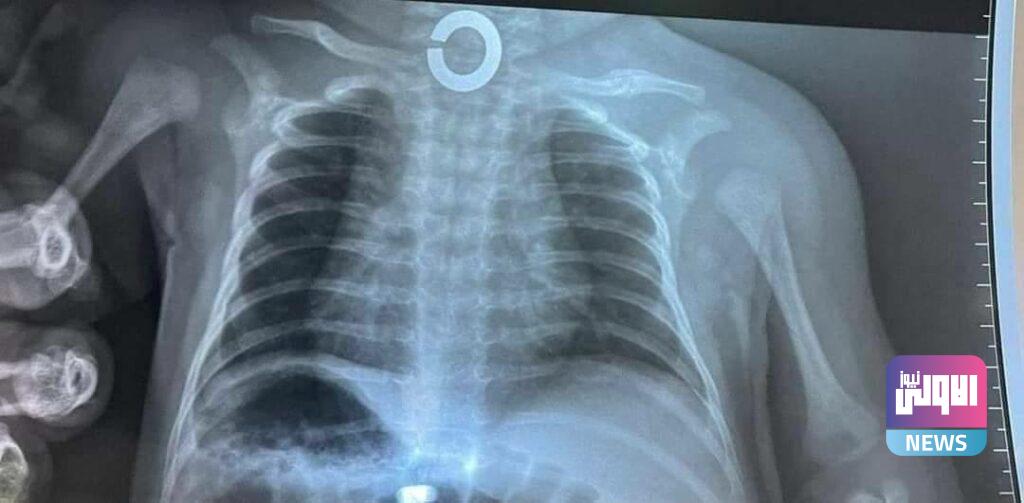

نجح فريق طبي بمستشفى امراض وجراحة الجهاز الهضمي في البصرة، اليوم الأربعاء، بانقاذ حياة طفل بعمر 30 يوما ابتلع قطعة معدنية.

وذكر بيان لوزارة الصحة، تلقته (الاولى نيوز )، أن “فريقا طبيا في مستشفى امراض وجراحة الجهاز الهضمي والكبد التابع لدائرة صحة البصرة نجح بإنقاذ حياة طفل بعمر 30 يوما محال من مستشفى المدينة العام قام بابتلاع قطعة معدنية استقرت في اعلى المريء “.

وذكر الطبيب المشرف الدكتور منتظر عبد الكريم اختصاص دقيق امراض الجهاز الهضمي والكبد: “تم اجراء ناظور طارئ تحت التخدير العام وتم اخراج الجسم المعدني بدون مضاعفات بجهود الفريق الطبي والصحي والتمريضي في المستشفى”.